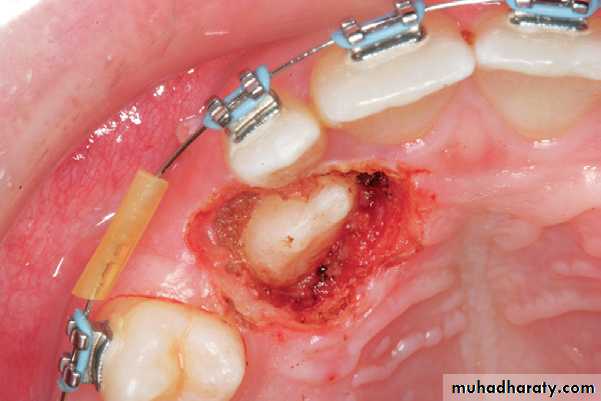

Clinical photograph of the area of impaction

Palatal incision along the cervical lines of teeth using a scalpel with a no. 15 blade

Reflection of the mucoperiosteal flap. Arrow points to the nasopalatine nerve

Removal of the bone covering the crowns of impacted teeth

Palatal impaction canineSurgical field immediately after exposure of

impacted teeth. Orthodontic brackets have been placed on exposed parts of the crowns of the teethSurgical field after suturing